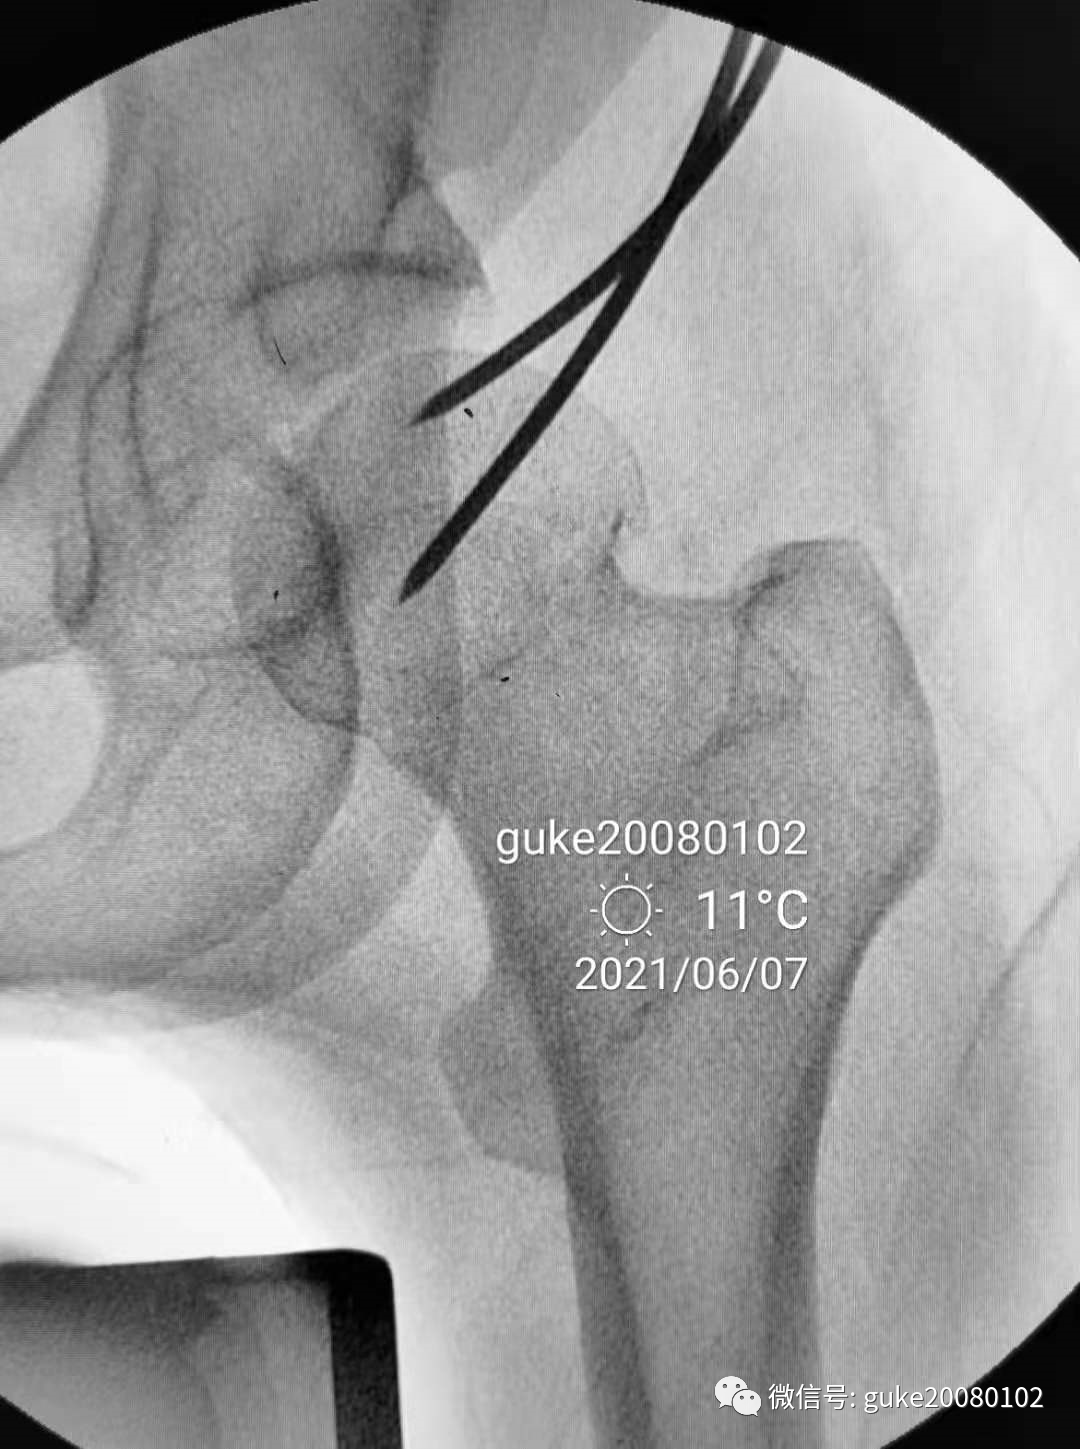

1.正侧位观察骨折复位,骨小梁走形恢复。崁插骨折复位。

2.外侧植入克氏针一枚,临时固定骨折。

1、植入的第一枚克氏针,前倾和颈干角均满意。将其作为标志针。

2、植入第二枚导针,调整前倾和颈干角。

3、数次调整三枚导针到最合适的位置。